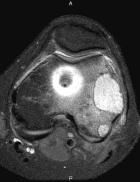

Patient is a 26 y/o male w/ hx. of polyostotic fibrous dysplasia s/p IM nailing for a pathologic L. femur fx. seven yrs. ago presents c/o 1 yr. hx. of increasing L. lat knee pain/swelling; PMH: polyostotic fibrous dysplasia and L. humerus fx; PE: L. knee w/ minimal effusion; +TTP over lat. condyle and w/ flexion to 100 deg; NVI